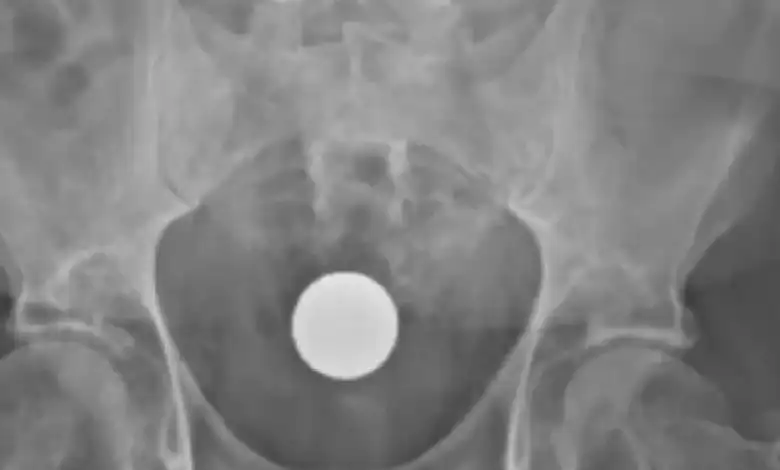

O homem chegou ao hospital com batimentos cardíacos acelerados e respiração ofegante. Após exames, a equipe identificou a perfuração intestinal e realizou uma laparotomia de emergência — cirurgia para abertura da cavidade abdominal. O procedimento permitiu a retirada dos ovos e a limpeza da área afetada, evitando que a infecção se espalhasse.